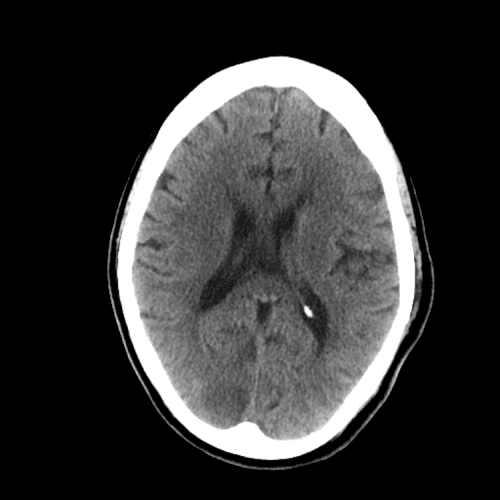

Non-traumatic Head CT Cases

Classic Cases

Includes classic examples of cases commonly seen on call.

ACA and MCA territory infarct

Case #1